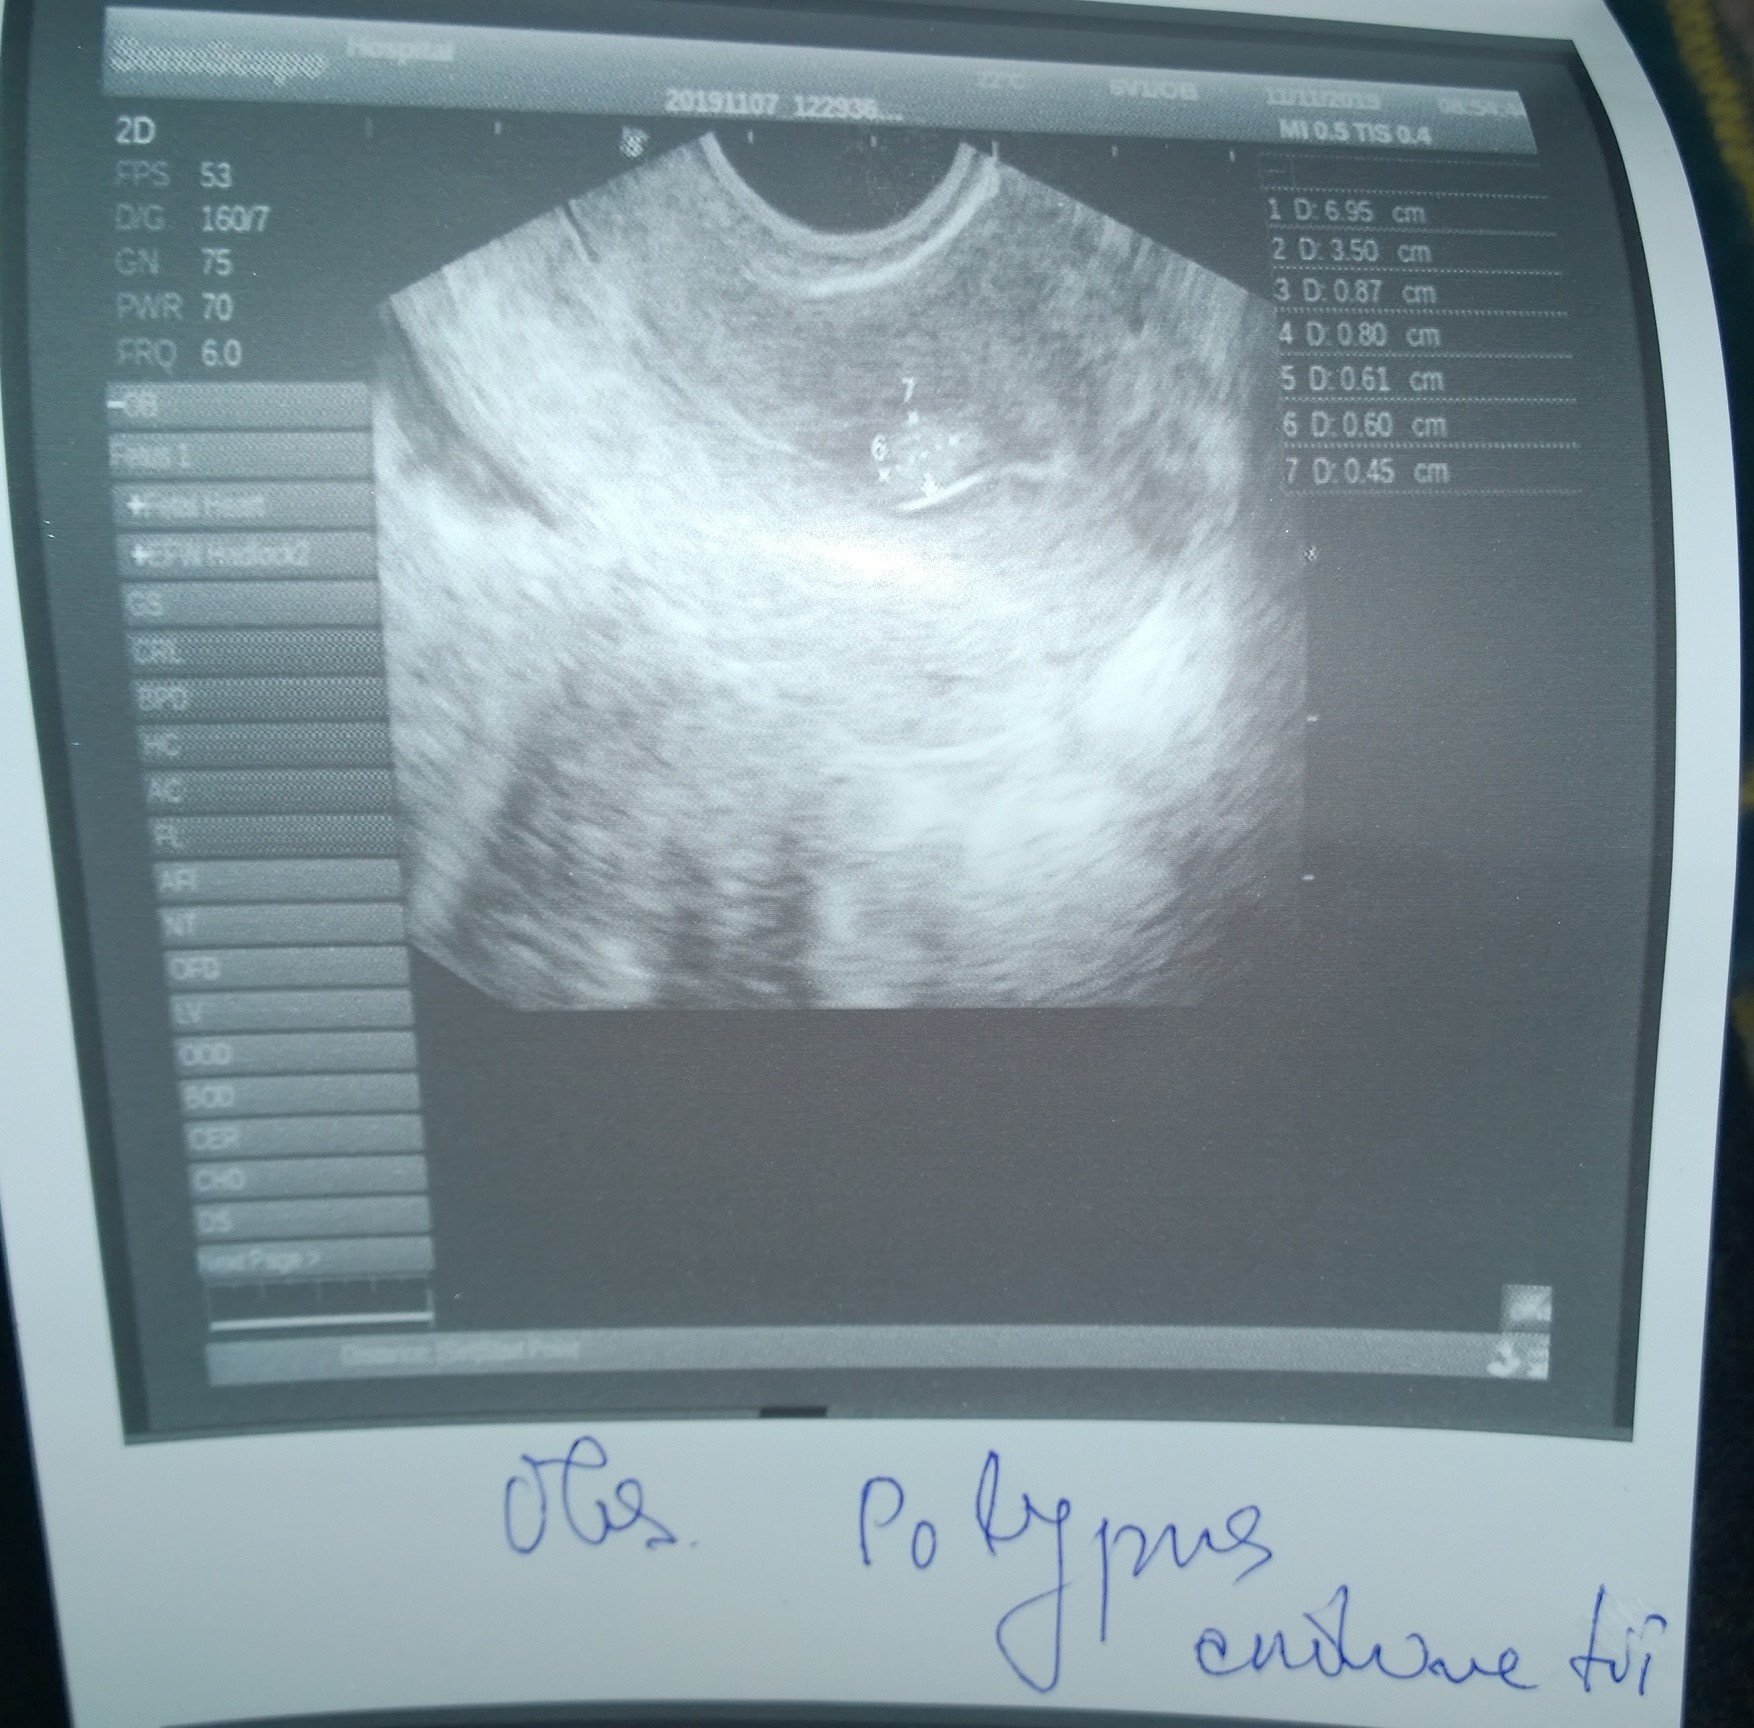

Хистероскопията е процедура, която включва директен оглед на маточната кухина с помощта на оптична система и осветление. Прилага се както за диагностични, така и за терапевтични цели при различни гинекологични състояния, като прекомерни или продължителни менструации, междуменструално кървене, нередовни менструални цикли, безплодие, съмнение за неправилно поставена вътрематочна спирала , съмнение за вродени маточни аномалии, съмнение за сраствания в маточната кухина и други. Хистероскопията е процедура, която включва използването на хистероскоп за изследване на вътрешността на матката. Извършва се с цел диагностициране и лечение на състояния като полипи, хиперплазия на ендометриума, рецидивиращи полипи и други проблеми, които могат да доведат до трудности при забременяване.